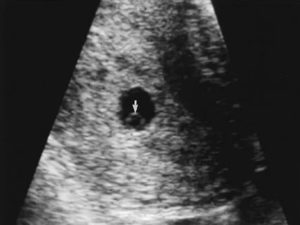

Желточный мешок на УЗИ

При ультразвуковом исследовании трансвагинальным датчиком желточный мешок определяется с 6 по 12 неделю беременности. Допускаются незначительные отклонения (до 2 недель) в любую сторону. Отсутствие на УЗИ желточного мешочка – неблагоприятный признак, свидетельствующий о серьезных нарушениях в течении беременности.

При проведении УЗИ врач оценивает расположение, форму и размер желточного мешка. Размеры желточного мешочка будут зависеть от срока гестации.

Так на УЗИ выглядит пустое плодное яйцо.